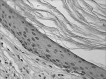

Material and methods: observational cross-sectional study, which analyzed 33 fragments of cholesteatomas through histological analysis and immunohistochemistry (using as primary antibody to TNF-R2 LabVision® brand). The evaluation was performed by means of a qualitative and semi-quantitative agreement with the observed intensity. For statistical analysis we used the Fisher exact test and Spearman's correlation coefficient (considered statistically significant when p < 0. 05).

Results: The expression of TNF-R2 was present in all fragments, however a statistical analysis showed no correlation or association between inflammation and the expression of TNF-R2.

Conclusions: TNF-R2 is present in cholesteatoma of the middle ear, however, its expression is not directly related to the degree of inflammation observed in patients with this disease.